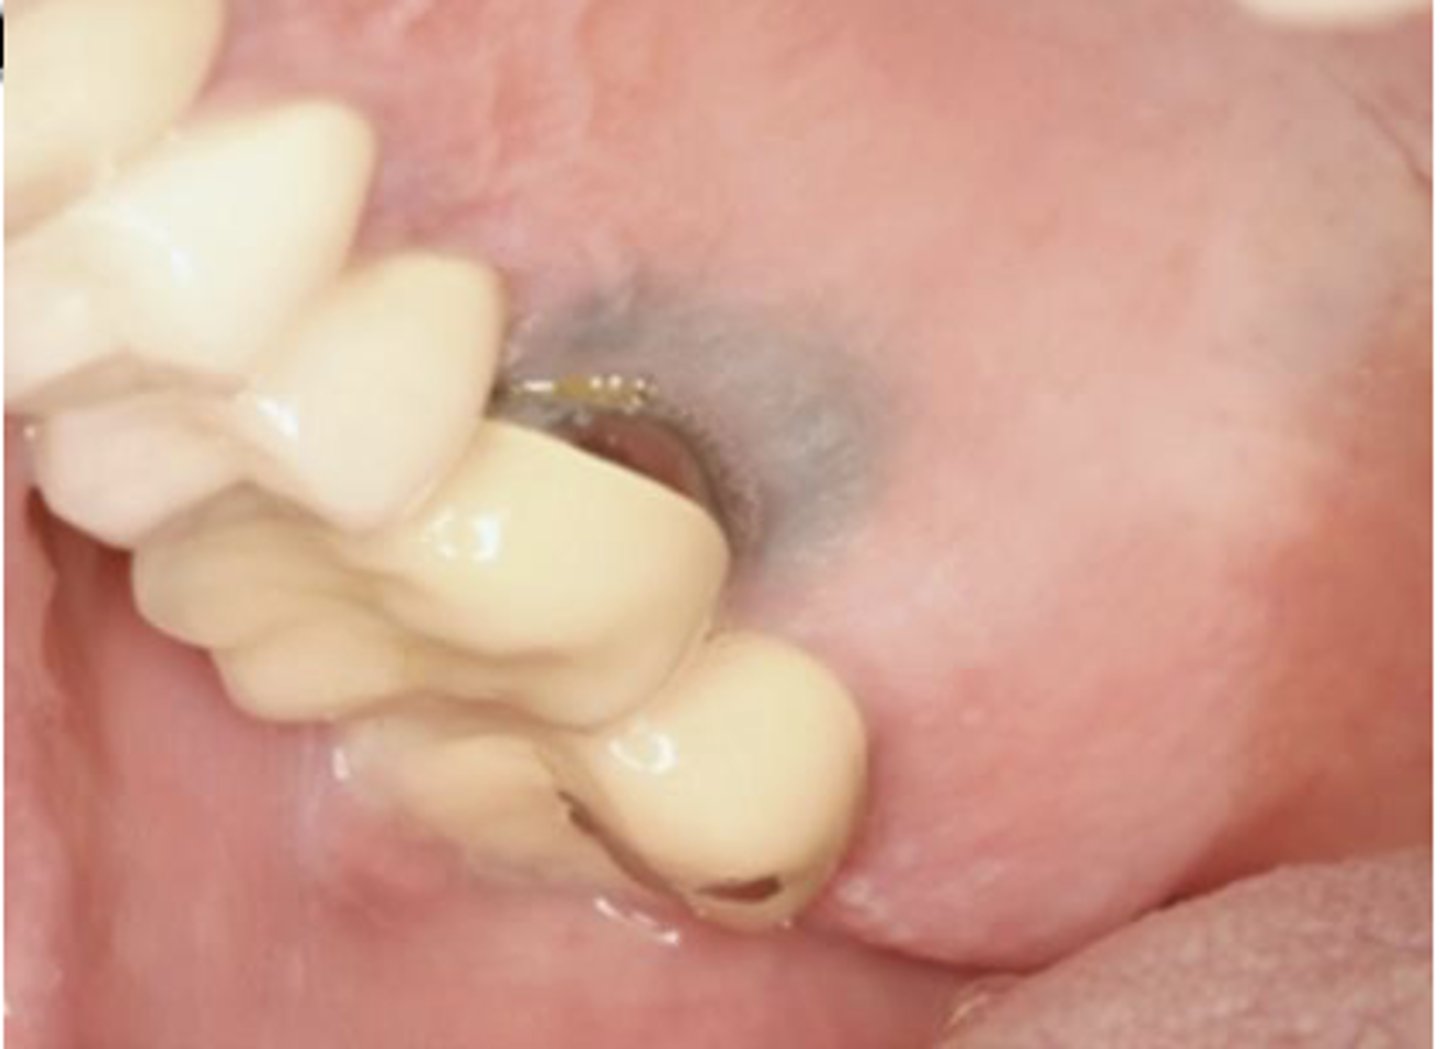

What type of pigmented lesion?

amalgam tattoo